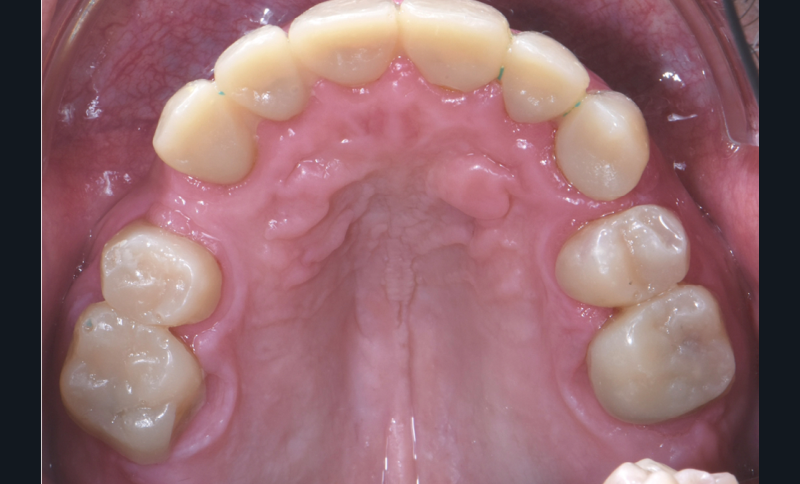

Au vu du contexte para-fonctionnel et de l’étendue de la perte tissulaire, des coiffes périphériques minimalement invasives ont été choisies afin de restaurer l’esthétique et la fonction. Actuellement, aucun consensus n’est fait sur le choix du matériau d’infrastructure à privilégier. Les matériaux hybrides usinables présentent des propriétés mécaniques, physiques et biologiques intéressantes en contexte d’usure sévère (e.g., module d’élasticité, résistance à la propagation de fêlures, facilité de réintervention). Une réhabilitation globale avec remontée de dimension verticale d’occlusion (DVO) par l’intermédiaire de coiffes composites renforcés en nano-céramiques est décrite.